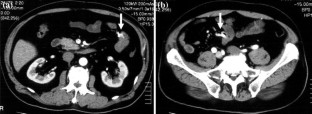

This report presents the case of a patient with Cowden syndrome who had arteriovenous malformations (AVMs) at the jejunum and the ileum and experienced intestinal bleeding. A 54-year-old Japanese male presented with general fatigue and melena. Endoscopic examinations showed gastrointestinal polyposis from the esophagus to the rectum. However, the site of bleeding was not identified. There were some papules on his face and neck. He also had macrocephaly and had multiple papillomas along the gum-line. These findings indicated a clinical diagnosis of Cowden syndrome. Enhanced computed tomography (CT) and angiography analyses indicated the presence of AVMs at the jejunum and the ileum. He was treated with partial resection of the jejunum and ileum including these two AVMs. This was a rare case of two AVMs involving the small bowel in a patient with Cowden syndrome. Enhanced CT was very useful and convenient for the detection of gastrointestinal AVMs in this case.

Fig. 1